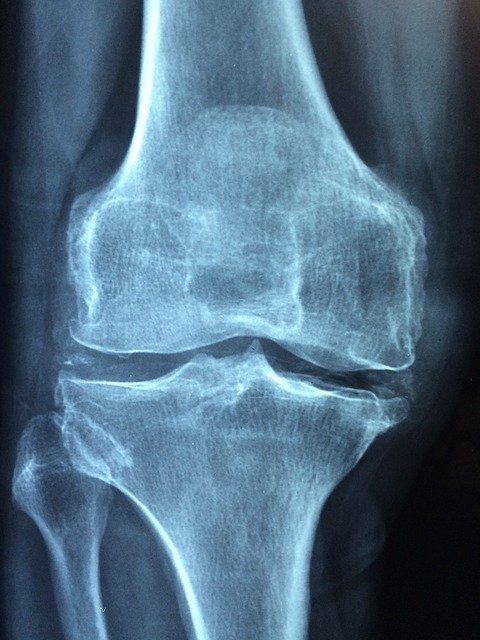

타트체리는 통풍에방에도 효과적인데, 관절염 및 통풍을 조절하는데 도움이 되는 항염증 특성을 가진 것으로 밝혀졌다. 류마티스 학회 (ACR)의 저널인 관절염&류마티즘에 발표된 연구결과에 따르면 체리를 섭취한 통풍 환자는 그렇지 않은 환자에 비해 통풍위험이 35% 낮은 것으로 확인 되었다.